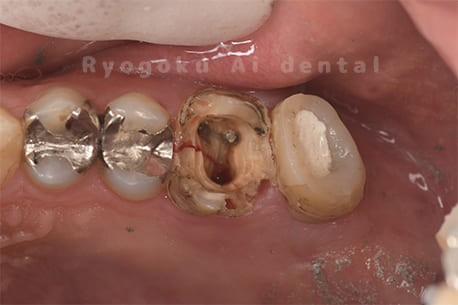

Case27

-

重度カリエス

歯牙移植術直後咬合面

歯牙移植術後咬合面

歯牙移植術前側面

歯牙移植術中側面

歯牙移植術後側面

- 原因

- 重度カリエス

- 治療内容

- 自家歯牙移植、部分矯正

- 治療費用

- 220,000円(移植費用)

110,000円(部分矯正費用)

虫歯が大きく、保存不可能となった歯を上の親知らずと交換する自家歯牙移植を行いました。移植歯が小ぶりであったため、部分矯正を行い問題なく噛み合い、経過良好です。